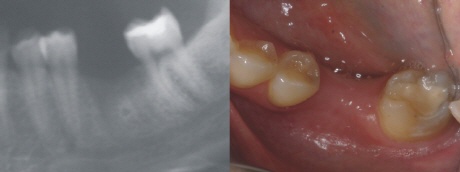

Ausgangssituation

Ein Zahn ist durch eine tiefe Karies verloren gegangen. Die Nachbarzähne sind nahezu unversehrt, nur der letzte Zahn hat eine kleine Füllung (weiß im Röntgenbild). Um weitere Folgeschäden zu vermeiden, entschied sich die Patientin für ein Zahnimplantat.